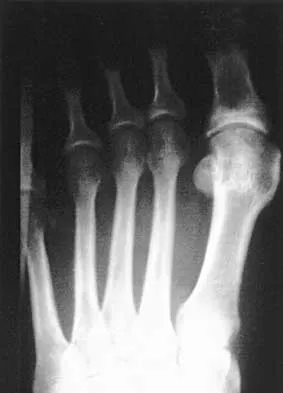

An 83-year-old woman with diabetes mellitus has a history of recurrent infection over the medial aspect of her great toe and has had a painless bunion for the past 45 years. Shoe wear modifications have failed to provide relief. Pedal pulses are palpable. Figures 30a and 30b show the clinical photograph and radiograph. Management should now consist of

Explanation

The presence of recurrent breakdown over the medial eminence despite shoe wear modifications is an indication for surgery. A number of factors must be considered when deciding on an appropriate course of treatment. These include age, activity level, joint congruency, joint degeneration, and the patient's symptoms and expectations. The indications for a simple bunionectomy are rather limited. In this patient, the goal of surgery is to alleviate the recurrent infection by removal of a large medial eminence. Because the bunion is painless and long-standing, it does not warrant treatment. Mizel MS, Miller RA, Scioli MW (eds): Orthopaedic Knowledge Update: Foot and Ankle 2. Rosemont, IL, American Academy of Orthopaedic Surgeons, 1998, pp 123-134.

References:

- Abidi NA, Conti SF: The clinical and radiographic anatomy of hallux valgus and surgical algorithm. Foot Ankle Clin 1997;2:599-626.